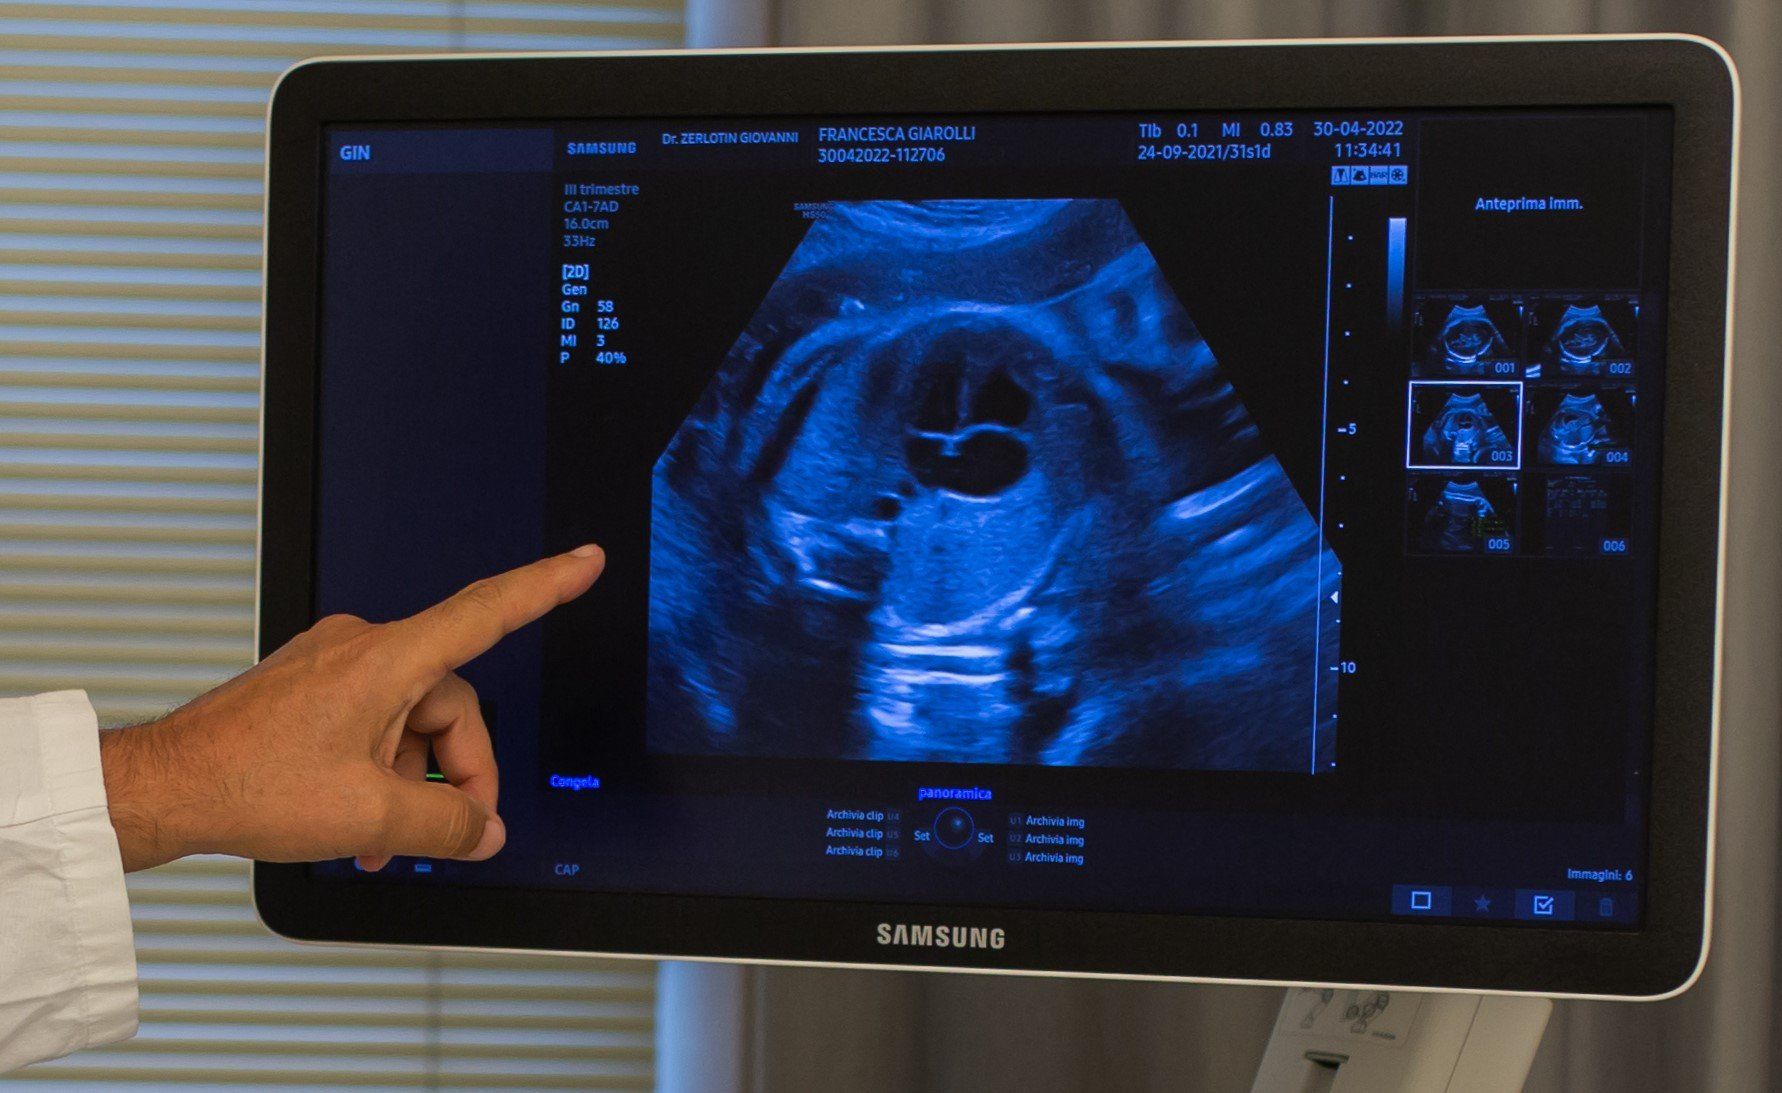

L’ecografia è una tecnica che consente di vedere gli organi del nostro corpo con l’utilizzo di onde sonore ad alta frequenza (ultrasuoni, non udibili dall’orecchio umano) che attraversano i tessuti. La sonda ecografica invia impulsi di onde sonore nel corpo. Quando le onde sonore arrivano al feto mandano degli echi: tali echi (o onde di ritorno) sono trasformati in immagini sul monitor dell’ecografo. Con l’ecografia è quindi possibile osservare in modo dettagliato il feto.

A fianco alla più tradizionale ecografia eseguita per via transaddominale, risulta particolarmente utile nell’esame ecografico ostetrico e ginecologico la via di accesso transvaginale.

Con questa metodica, utilizzando delle sonde ecografiche appositamente predisposte (per forma e dimensione, e per frequenza di emissione degli ultrasuoni) è possibile controllare la gravidanza nel primo trimestre con una qualità e definizione d’ immagine nettamente superiori a quanto possibile per via transaddominale.

Con il finire del primo trimestre per il controllo ecografico di routine della gravidanza la via transvaginale viene poi sostituita dalla via transaddominale.